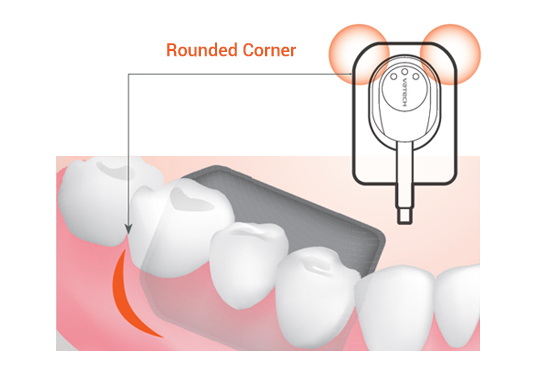

2. DISEÑO ORIENTADO AL PACIENTE

El diseño de esquinas redondeadas permite una colocación cómoda máxima contra el tejido blando.

- Los pacientes sienten dolor porque la delicada mucosa oral recibe presión de una esquina dura del sensor. La esquina redondeada puede reducir ese dolor. Pero tiene la posibilidad de reducir el área activa de la imagen. Esta es la tecnología que sostiene el equilibrio perfecto entre ellos.

- Los sensores de diseño ergonómico en 3 tamaños diferentes satisfacen las necesidades de varios casos. Los bordes redondeados y cortados brindan la mejor comodidad posible a los pacientes. El sensor de tamaño 1.5 único de Vatech se adapta a casi todos los pacientes.